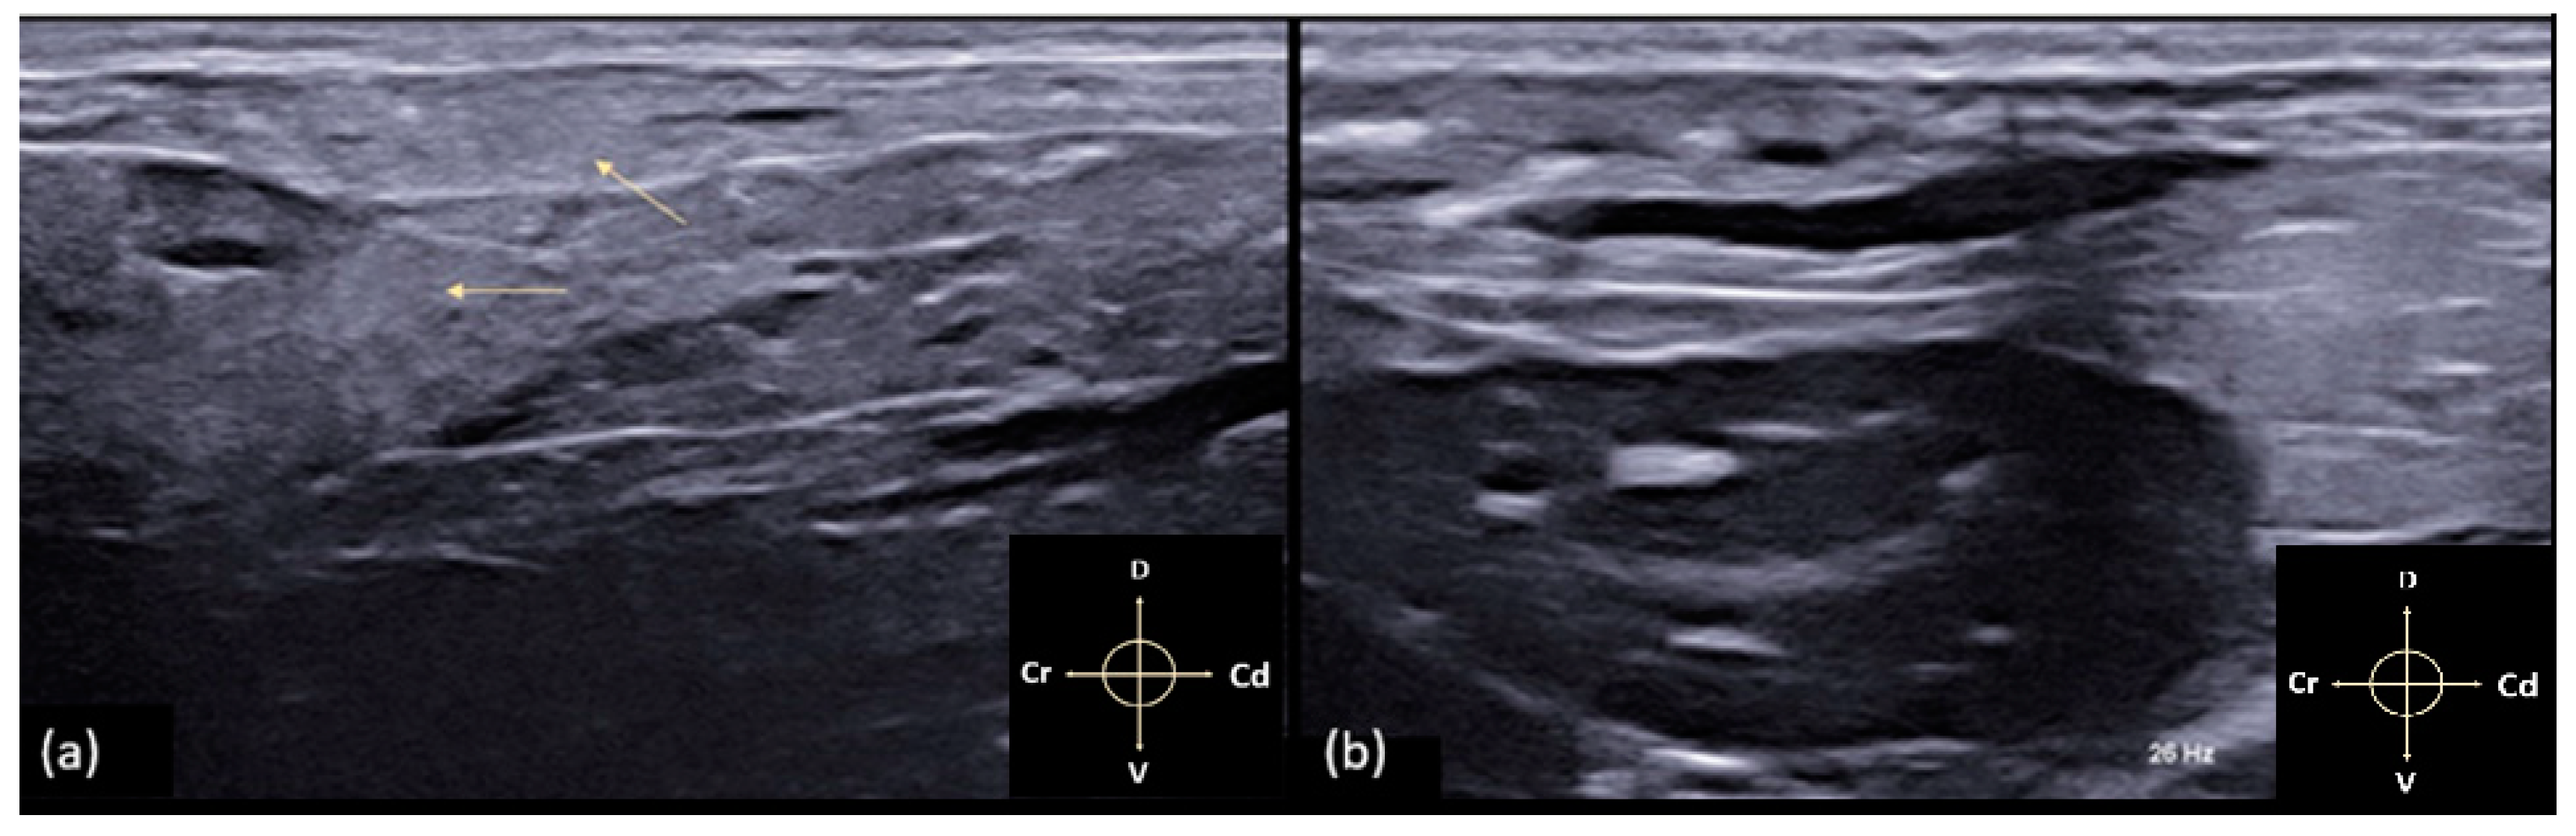

2.2. Anatomical Dissection

3.2. Anatomical Dissection